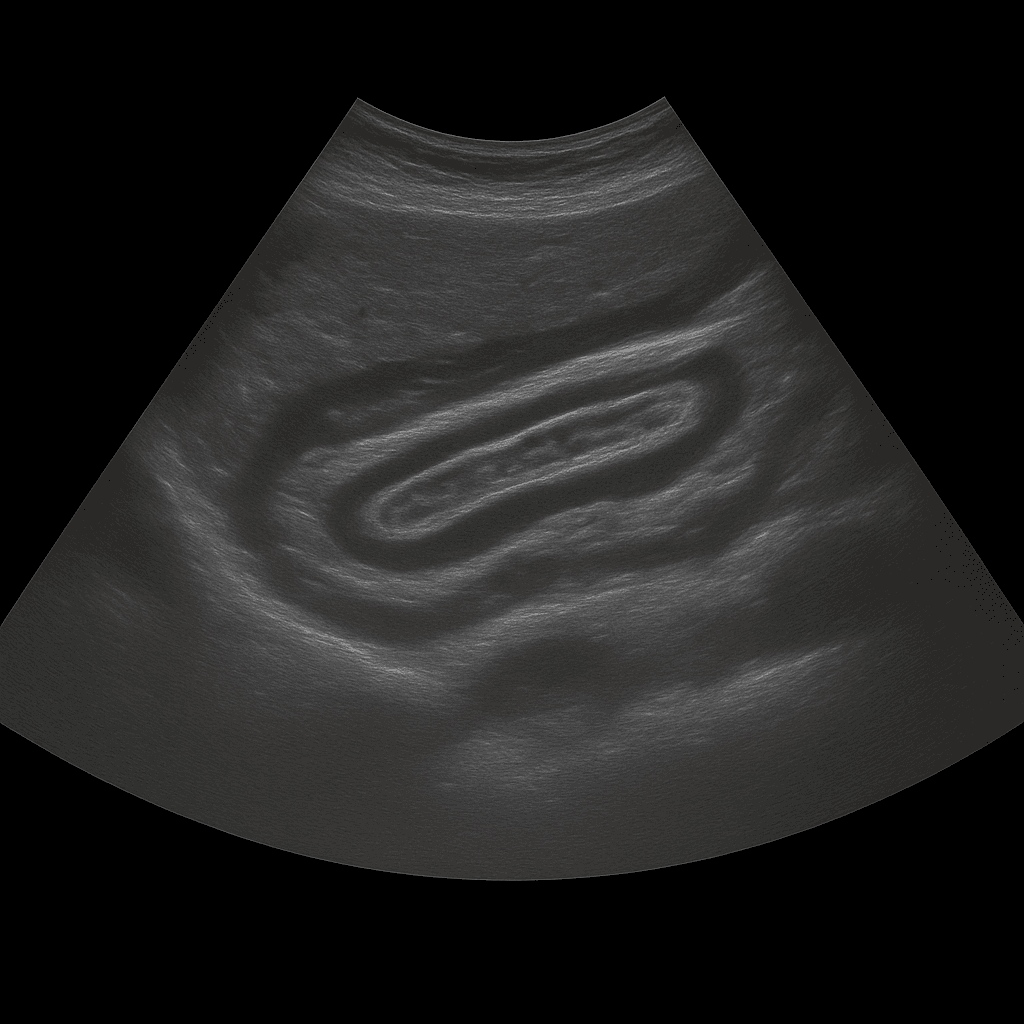

Ett ultraljud av buken används för att undersöka bukens inre organ såsom lever, gallblåsa, gallvägar, bukspottkörtel, mjälte, njurar och urinblåsa. Undersökningen utförs av specialistläkare inom radiologi och ger detaljerade bilder i realtid. Ultraljud buk används för att utreda smärta, svullnad, förändrade blodprover eller misstanke om sjukdom i bukorganen.

Till skillnad från MR och DT, som används för mer detaljerad kartläggning av djupare vävnader eller spridning av tumörer, är ultraljud den primära metoden vid initial utredning av bukbesvär. Metoden är snabb, strålningsfri och visar förändringar i realtid – vilket gör den särskilt värdefull vid bedömning av gallvägar, njurar och vätskeansamlingar.

Undersökningen utförs när du ligger på rygg. En gel appliceras på huden och läkaren för ultraljudsproben över bukområdet för att bedöma de inre organen. Undersökningen tar cirka 20–30 minuter och är helt smärtfri. För bästa bildkvalitet bör du vara fastande i 4–6 timmar innan, eftersom luft och föda i tarmen kan påverka bildresultatet. Vid behov undersöks även urinblåsan fylld för att bedöma njurarnas avflöde.